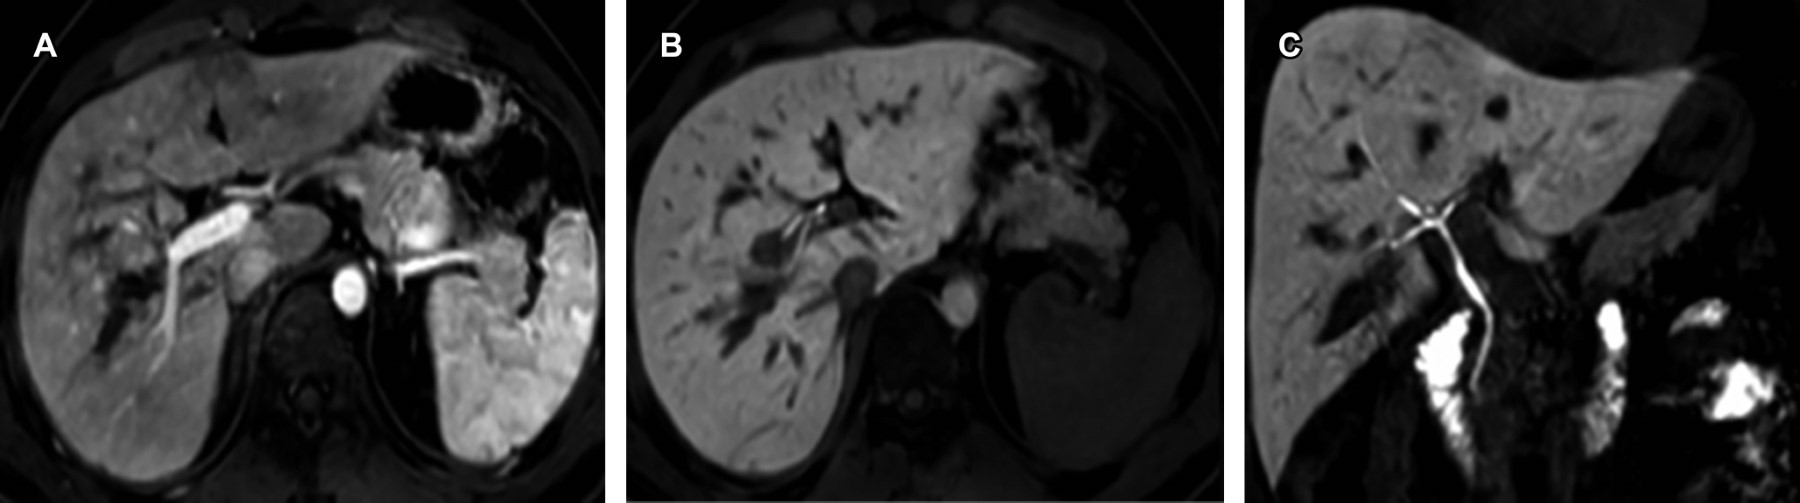

This is a 30-year-old male patient who, after suffering a three-story fall, showed hepatic contusion on CT scan and ultrasound. MRI with gadoxetic acid demonstrated laceration, vascular integrity, and biliary anatomy without evidence of injuries.

Figure 1